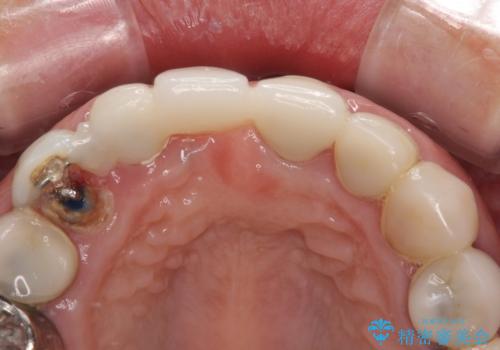

問題の歯は、歯根まで破折している状態で、抜歯が必要と判断されました。

周辺の歯は20年以上前に装着したクラウンで、色合いや形態が気になっているとのことで、オールセラミックブリッジにて補綴治療を行うこととしました。

ところが、土台となる歯は、十分な維持力が得られないほど歯ぐきの中に埋もれており、歯ぐきも腫れやすい状況でした。

まずは土台の歯を引っぱり出し、外科処置により歯肉の状態を十分に整えた上で、オールセラミッククラウンにて補綴することとしました。